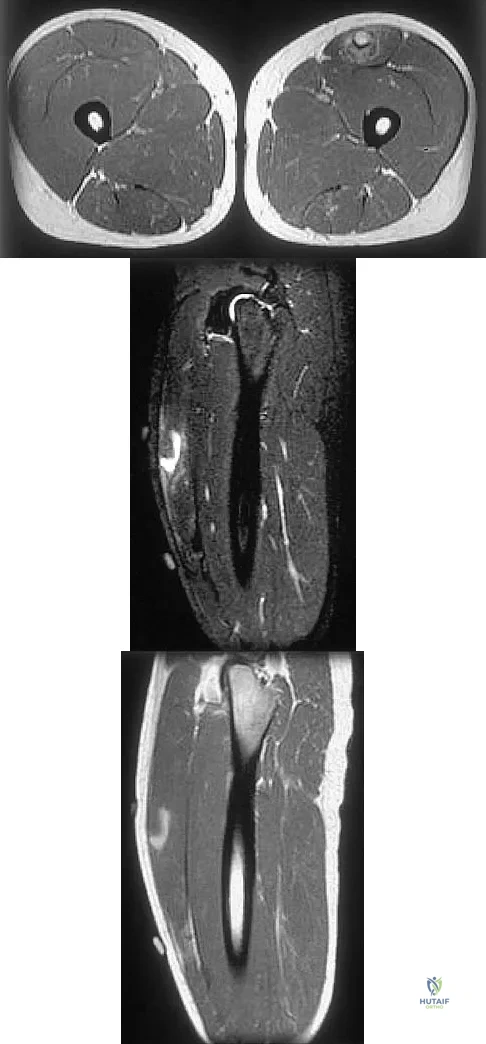

Figures 34a through 34c show an axial proton density (spin echo long TR, short TE) image, a sagittal inversion recovery (STIR) image, and a sagittal T1-weighted (short TR, short TE) image of the left thigh. What is the most likely diagnosis?

Explanation